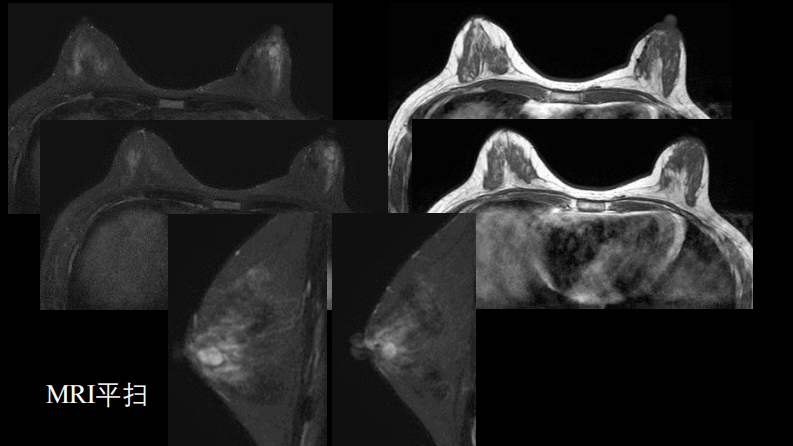

乳腺囊性肿块MRI:鉴别不困难.pdf

乳腺